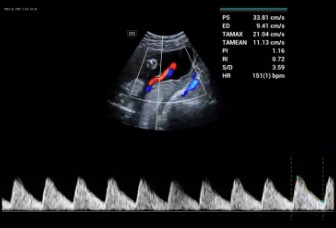

The Consona features new and concrete solutions, that efficiently help you to carry out smooth diagnoses for extensive type of patients. You will find highly powerful tools available on this series to keep you stay ahead in Obstetrics and Gynecology diagnosis.

Image Gallery